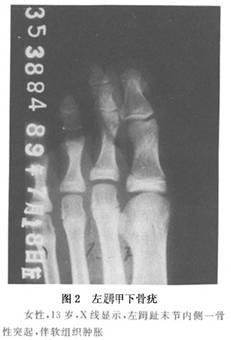

骨軟骨瘤在手、足小骨上其X線表現類似於在長管狀骨的表現。值得注意的是,在指、指末節可有小的骨軟骨瘤存在,稱爲甲下骨疣(圖2)。

手術時應將腫瘤充分顯露將骨膜、軟骨帽蓋、骨皮質及基底周圍正常骨質一併切除。手術中容易出現將腫瘤表面骨膜剝離不淨和腫瘤基底周圍正常骨質切除過少,而遺留有骨的突起。手術切除徹底,一般不再復發。而甲下骨疣,手術雖小,但應徹底切除,否則易復發。